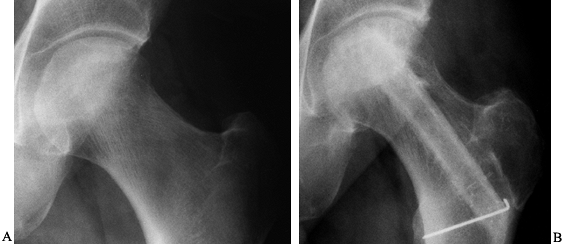

bearing for 2 months and then advance to a cane until union is visible

on radiographs (Fig. 125.21), usually 4–6 months after the procedure.

![]() |

Figure 125.21. Radiographs of a hip that underwent a varus osteotomy for osteonecrosis. A: Preoperative status. B: Six months after osteotomy. C: Ten years after surgery. The hip continues to function satisfactorily, although degenerative changes were eventually present.

|